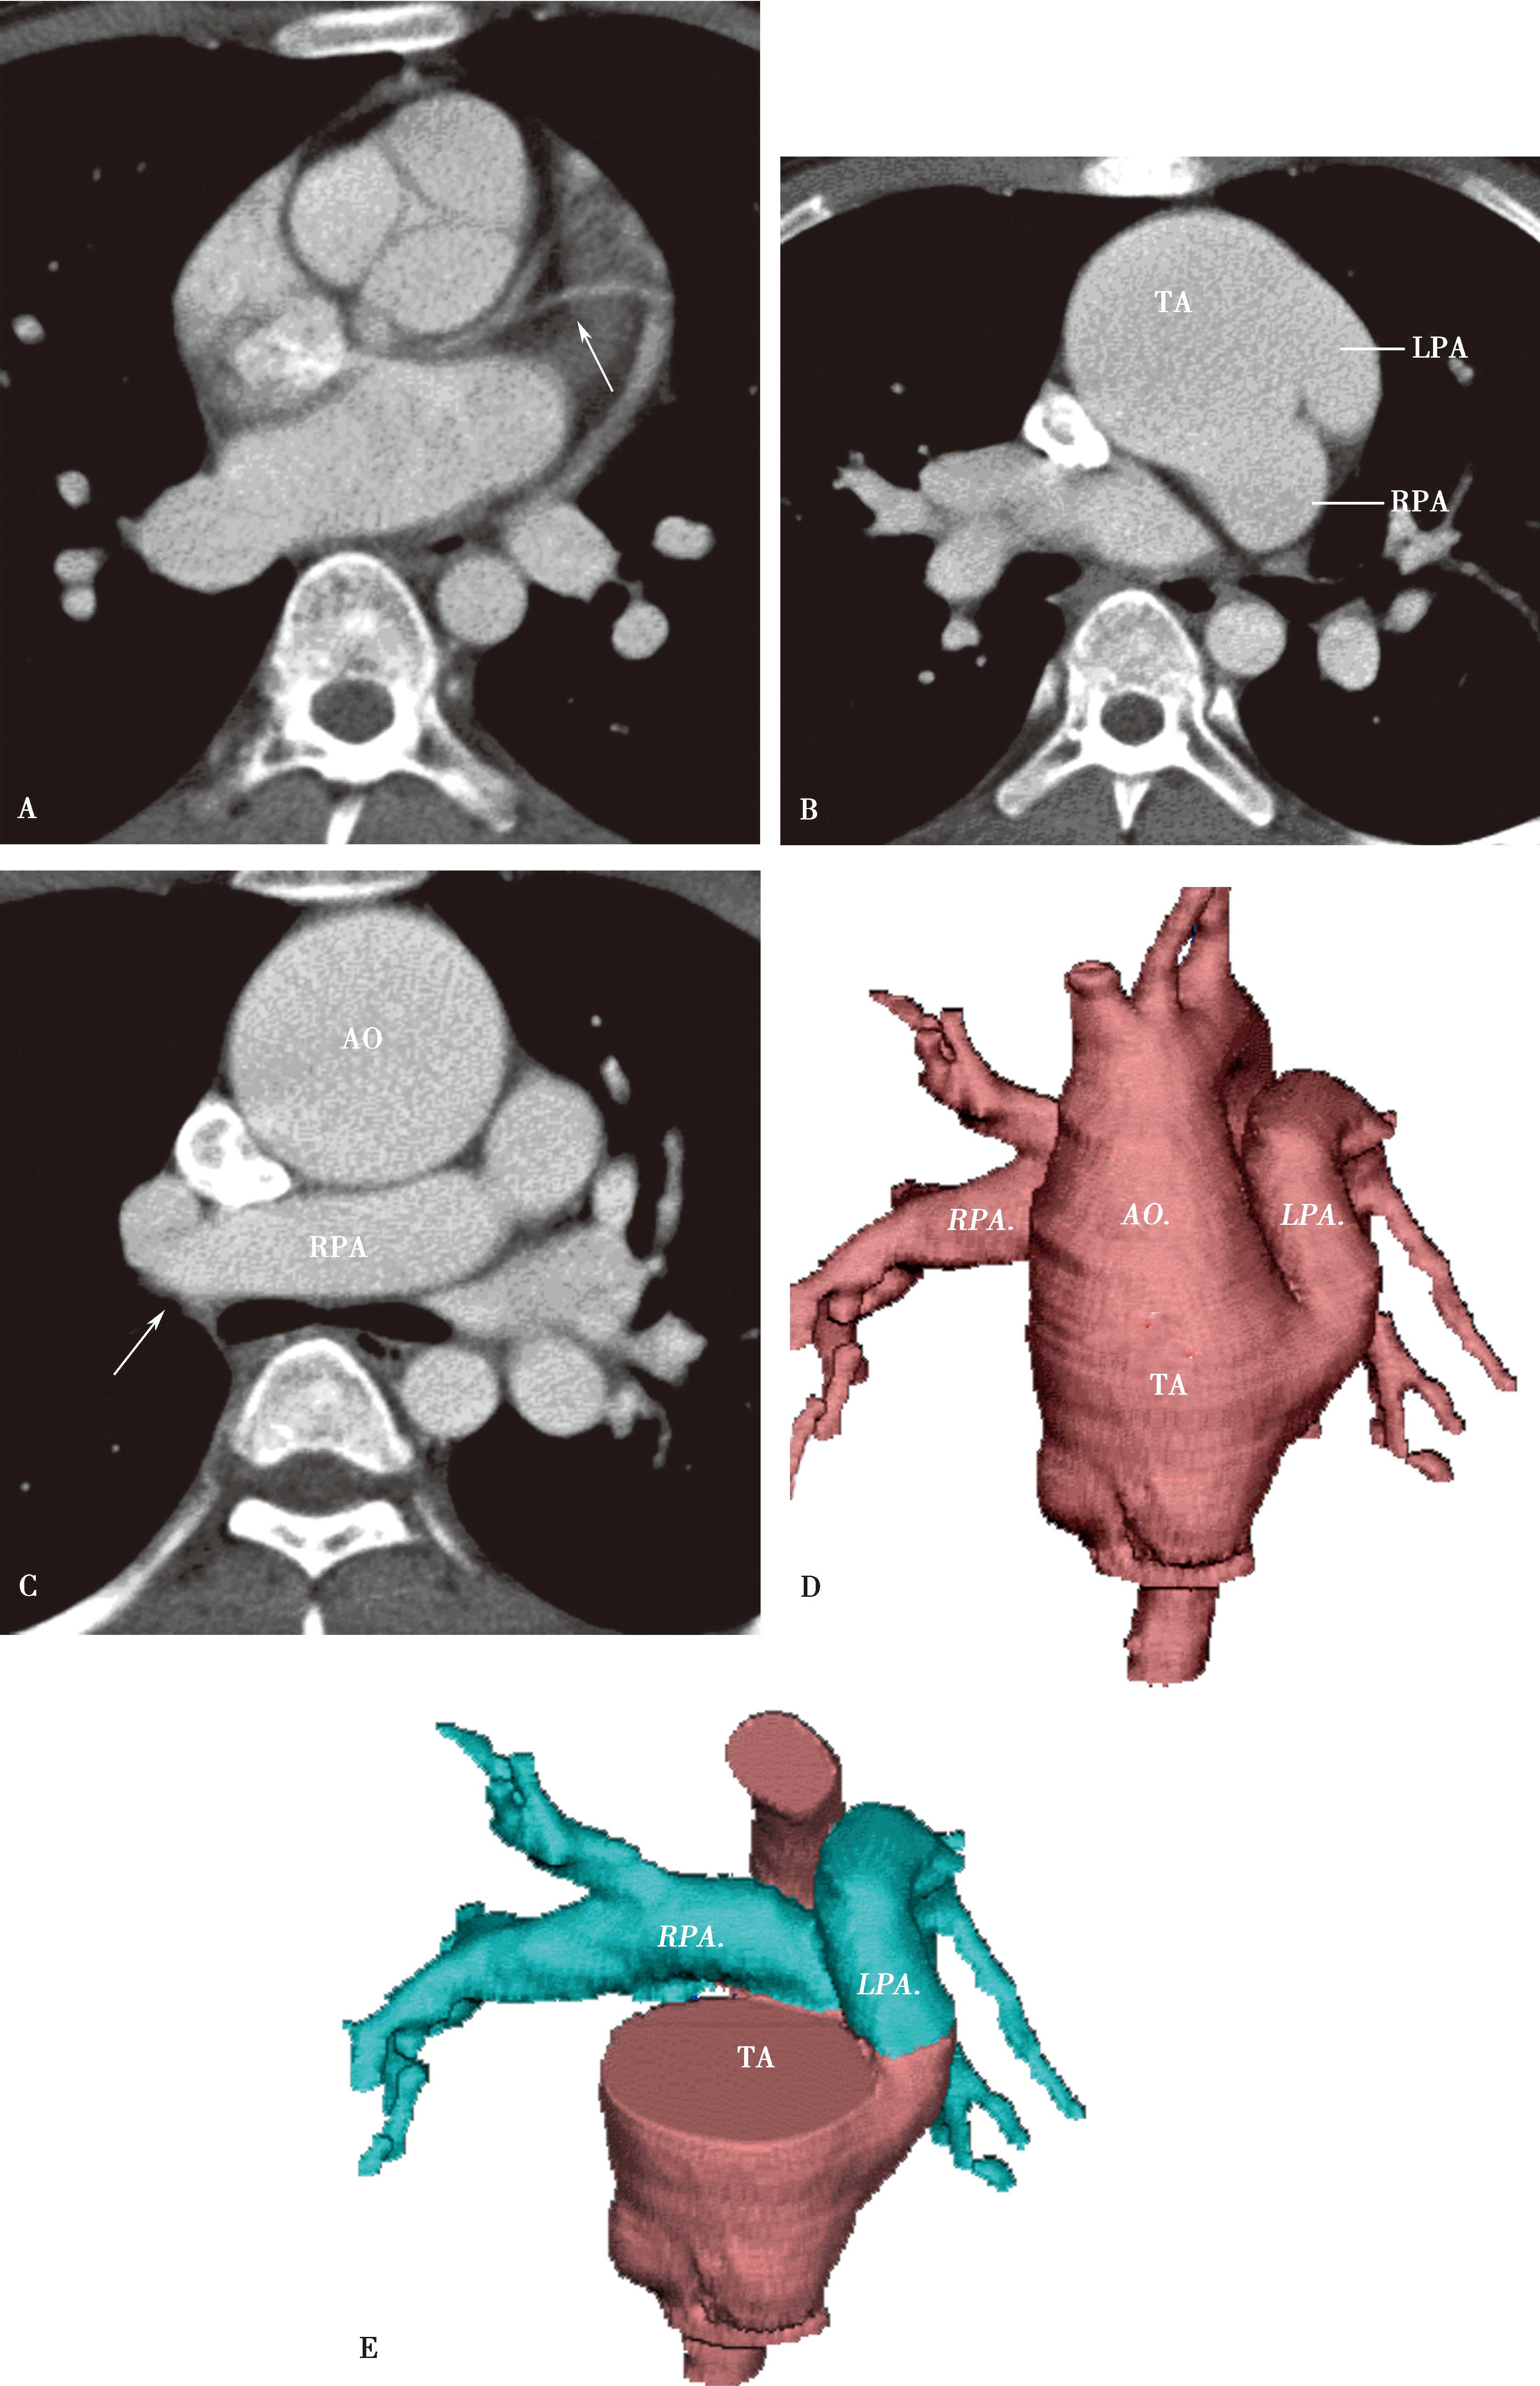

高分辨率CT(平扫)对诊断有重要价值。显示肺实质多发性斑片状、大小不等结节及空洞形成,主要分布两肺中下野,多发性/多样性(不规则,多发,大小不等)为其特点,并存胸膜反应,胸腔积液(图8-5-6)。

图8-5-6 坏死性肉芽肿性血管炎(韦格纳肉芽肿)

A.胸部X线片,两肺多发结节,不规则空洞形成(↑);B~D.横断图像,两上、下肺多发不规则结节肿块,大小不等,不规则空洞形成,壁薄厚不一,边缘不规则,液平形成;病理检查:E.肺小血管横断面,显示炎性细胞浸润累及部分血管;F.肺小血管纵切面,炎性细胞浸润,部分管壁破坏。CT诊断:韦格纳肉芽肿(病理证实为坏死性肉芽肿性血管炎)

(2)坏死性肉芽肿性肺血管炎(韦格纳肉芽肿):